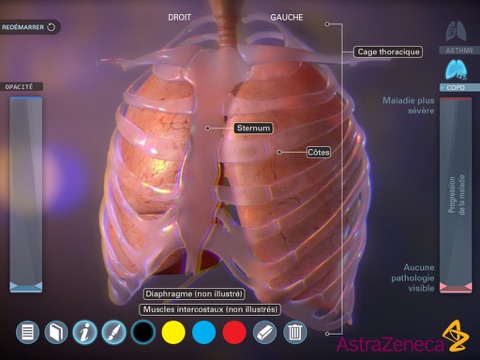

Living Lung est une application développée par AstraZenecaet destinée aux médecins. Elle présente en 3D lapparence des poumons des malades atteints dasthme ou de Broncho-Pneumopathie Chronique Obstructive (BPCO) en fonction de lévolution de la maladie.

Cette application, qui contient également des légendes anatomiques et un outil de dessin, est un support pour expliquer aux patients leur maladie.